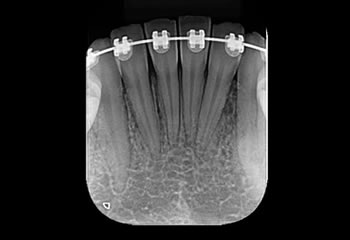

Radiografias Periapicais

Técnica radiográfica intrabucal, esta técnica possibilita uma visão dos elementos dentais da região de incidência e tecido ósseo adjacente.